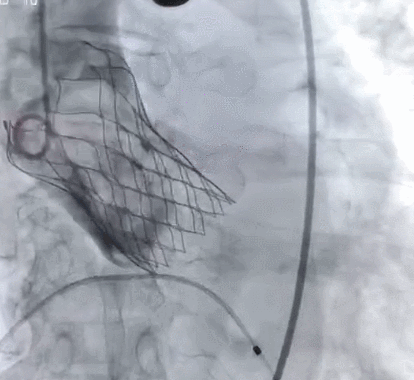

术后即刻:无瓣周漏,舒张压明显改善至68mmHg

术后造影